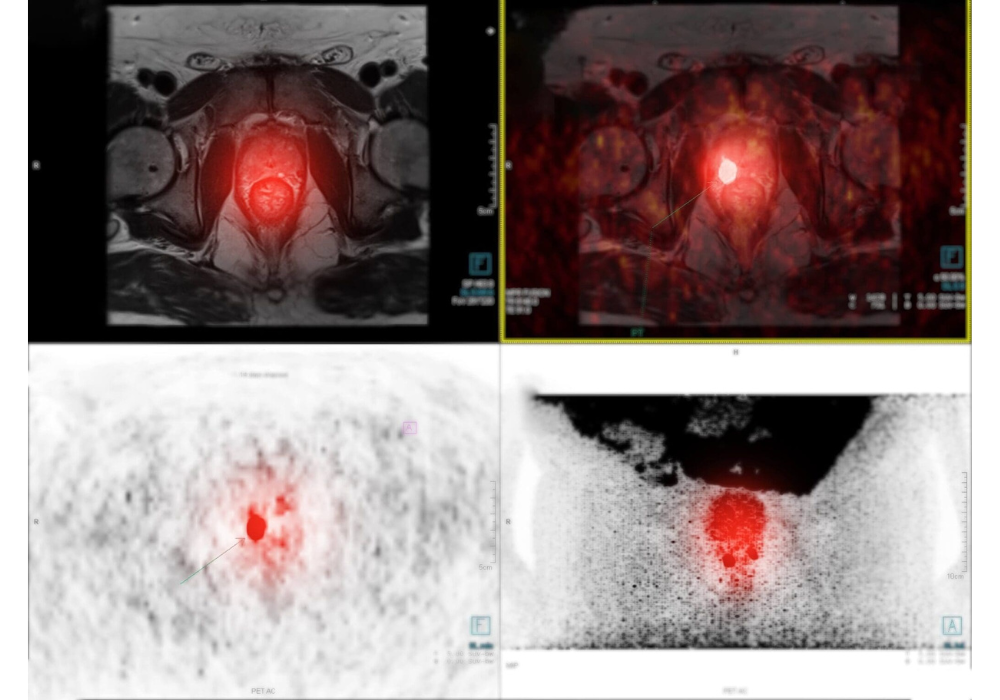

Radiology reading rooms are intentionally dim to optimise image contrast and reduce glare, supporting accurate interpretation. However, prolonged time in such settings coincides with reduce